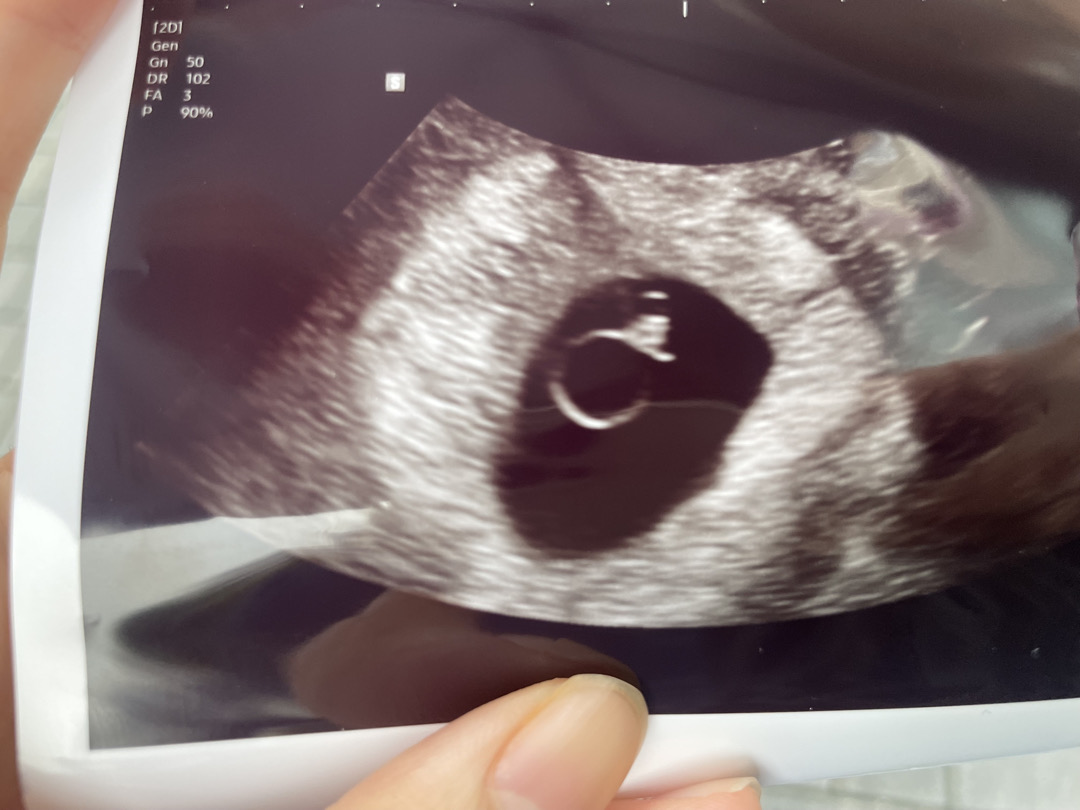

저는 오늘 7주3일인데 5주1일때 아기집만 확인했고 2주만에 오늘 초음파 봤는데 초음파상 6주1일이고 난황이랑 아기는 확인했는데 아직 아기가 작다고 일주일뒤에 더 보자고 하셔서 심란해요 ㅠㅠ

7주 4일차 병원에서 아이가 주차별로 자라는 속도보다 느리대요

심장 소리를 아직도 못듣고 있고 아이 사이즈도 주차별로 자라야되는 속도가 있는데 너무 작다고 하는 상황이에요 그래서 선생님 말로는 물음표가 뜨는 상황이고 아직 이렇다 저렇다 말할수가 없대요 이유는 심장깜빡임이 보이는 상황이고 아기가 보이는 상황이긴해서요.. 근데 너무 불안하네요 … 저처럼 비슷했던 분 계실까요?